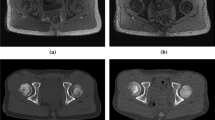

One patient had a joint facet defect meeting the criterion of ≥ 3 mm, seen on both sCT and CT (Fig. 2). There were multiple irregularities seen on sCT and CT on the iliac and sacral side of the SI joint that did not meet the criterion of ≥ 3 mm (Fig. 3).

Comparison between MRI-based synthetic CT (sCT) (a, c) and CT (b, d) in a 15-year-old girl in a paracoronal plane. Arrows indicate ossified nuclei. Also note the irregularities seen on sCT and CT (arrowheads) on the iliac side of the sacroiliac (SI) joints, these did not meet the criterion of ≥ 3 mm for joint facet defect

Subjectively, in some cases, the sCT images even demonstrated sharper cortical delineation than the CT and PET-CT images (Fig. S2). This made ossified nuclei and growth plates better visualized and more sharply delineated on sCT than on CT (Figs. 3, 4, and 5), explaining partly the variability in measurement of S1 and S2 vertebral bodies between sCT and CT. Suboptimal CT scan images may be due to the use of low-dose protocols conforming to the ALARA principle (as low as reasonably achievable), in which the lowest possible radiation dose to achieve the clinical diagnosis is used, which does not necessarily provide excellent images for evaluation of bony structures [19, 20]. This may explain why measurements of S1 and S2 vertebral bodies were not within the 1 mm equivalency margin, especially the endplate of the S2 vertebral body which was sometimes difficult to see on a midsagittal plane.

The ongoing ossification process in children can result in unsharp cortical margins, making cortical assessment difficult. Multiple irregularities of the SI joints were seen in our study that did not meet the prespecified size definition of ≥ 3 mm (Fig. 3). Only 1 cortical irregularity met the definition and was observed on sCT as well as on CT by both readers (Fig. 2).